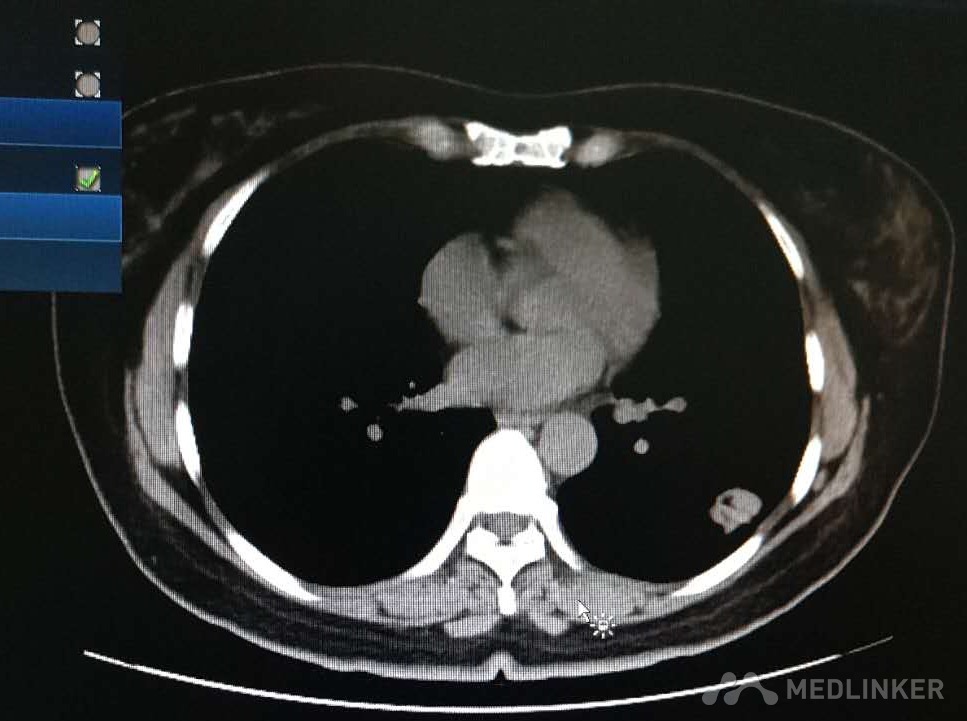

左肺下叶癌

患者,男,45岁 主诉:体检发现左肺下叶占位10天 现病史:患者于2周前体检行CT检查发现左肺下叶占位,于我院行PETCT检查,结果待回报,现为求进一步诊治来我科,病来饮食睡眠可,二便如常,体重近期无明显变化 既往史:一般健康状况:良好          药物过敏史否认          传染病史:否认肝炎结核病病史 预防接种史:按计划          手术外伤史:无,          输血史:否认        疾病史:否认 个人史:出生地—         迁徙史:无 冶游史:无         嗜烟嗜酒:无         职业及工作环境:无烟尘、无毒物及放射性物质接触史         婚姻史:结婚年龄:适龄岁 配偶健康状况:良好 其他:无 家族史:父亲:健康    母亲:健康               子女:健康 兄弟姐妹:健康               家族遗传病史:否认               家族中传染病史:无

初步诊断:左肺下叶占位 确定诊断:左肺下叶癌 治疗:胸腔镜下左肺下叶基底段局部切除,纵隔淋巴结廓清术 麻醉:全麻

患者术后生命体征平稳,于院内接受进一步治疗